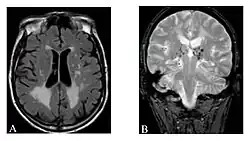

-

Die axiale MRT des Gehirns eines 27-jährigen Morbus-Fabry-Patienten mit ischämischem Schlaganfall zeigt den Schlaganfall in der linken zerebellären Hemisphäre. Der Patient wies sonst keine Symptome der Erkrankung auf. -

Hyperintensitäten der weißen Hirnsubstanz, lakunare Hirninfarkte und Mikroblutungen.

A) Die axiale MRT zeigt vielfältige Läsionen der weißen Hirnsubstanz in der zerebralen Hemisphäre eines 53-jährigen männlichen Patienten mit einem Fazekas-Score von 3.

B) Lakune und Mikroblutungen bei demselben Patienten. -